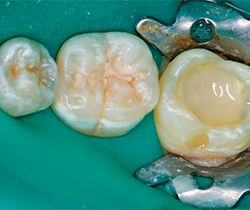

Fig. 1 Fig. 2

Under rubber dam isolation (Hygenic Non-Latex Dental Dam, Coltene Whaledent), the caries were removed and the teeth restored one quadrant at a time. A carbide bur was used to remove caries, followed with a diamond to bevel the cavosurface margins and finally with a round bur to excavate the deepest portion of the decay (Figs. 6-7).

Fig. 3 Fig. 4